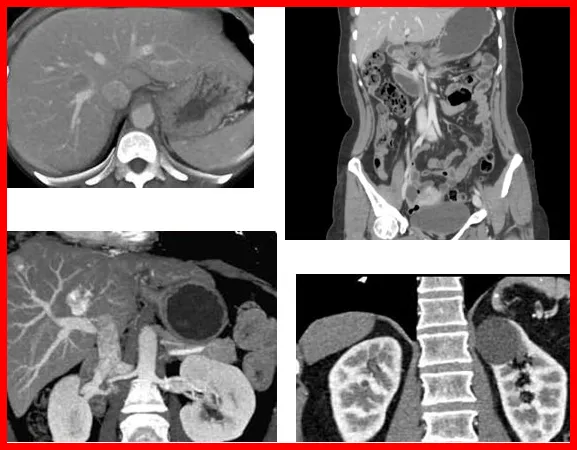

복부 CT 검사비

장기 상태 확인을 위해 사용된다. 조영제 사용 여부에 따라 검사비 차이가 발생한다. 검사 범위가 넓을수록 비용이 높아질 수 있다.